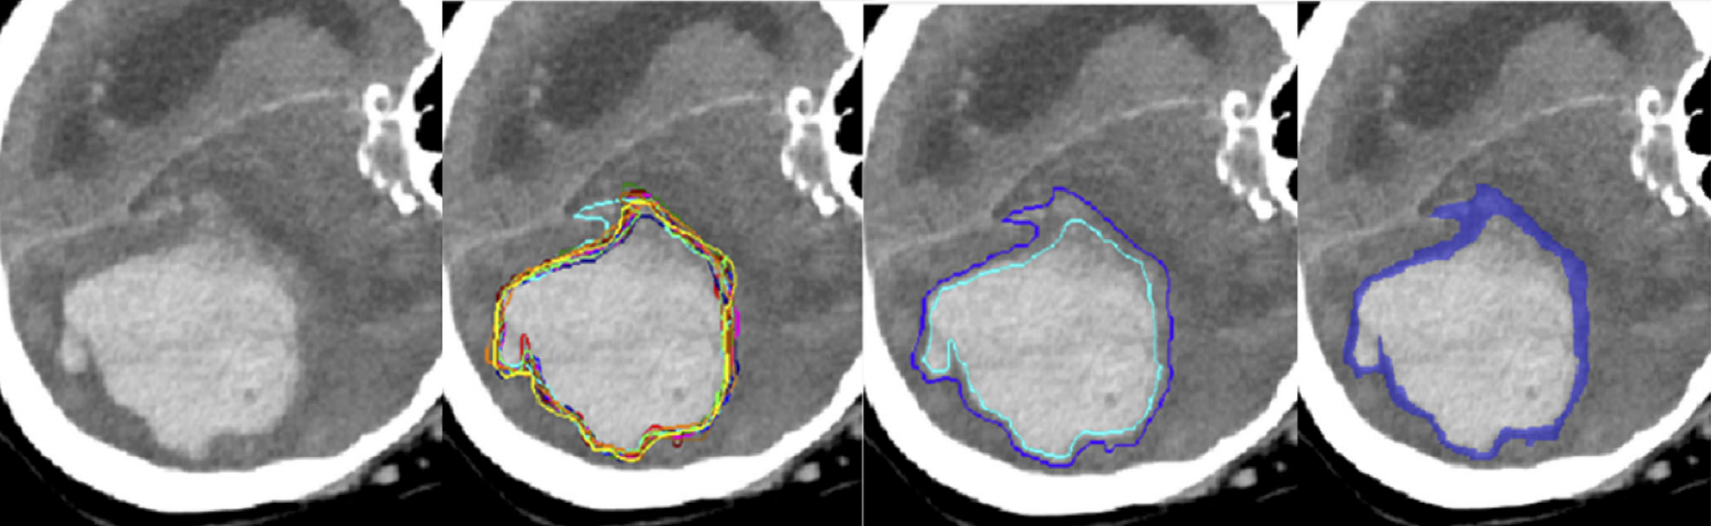

The QUBIQ challenge deals with benchmarking algorithms that quantify uncertainties in biomedical image segmentation. Participants will work on binary segmentation tasks, all of which with multiple annotations from domain experts. To be segmented are various pathologies and anatomical structures, such as brain, kidney, or prostate, in MR or CT image data. A successful algorithm will be able to segment these structures, and to reproduce the distribution of the experts’ annotations.